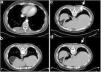

(a) CTPA revealing a right sided, well circumscribed, pleural based, soft tissue mass. (b) CT in prone position after CT guided FNB was completed, showing mass with lateral paravertebral displacement. (c) Patient in the prone position, the needle inserted during CT guided FNB (the arrow shows the insertion point). (d) The same level as (c), right after removal of the needle when CT guided FNB was completed (the arrow shows the point where the needle was previously inserted). Apart from lateral displacement shown in (b), craniocaudal displacement of the mass is evident too.

Patient underwent CT guided fine needle biopsy, in prone position, when insertion of the needle resulted in translocation of the mass in the pleural space (Fig. 1c: on needle insertion and Fig. 1b and d: right after removal of the needle), despite absence of complications during the procedure. Biopsy revealed a Solitary Fibrous Tumor (SFT) of the pleura and patient was referred for surgical treatment. Intraoperatively, a mass in the pleural space with a pedicle originating from the visceral pleura was resected.

A Computed Tomography Pulmonary Angiography (CTPA) was performed for a previously healthy, 45-year-old male patient with chest pain and high clinical suspicion for pulmonary embolism (PE). CTPA revealed a right sided, well circumscribed, pleural based, soft tissue enhancing mass (Fig. 1a) and no evidence for PE.